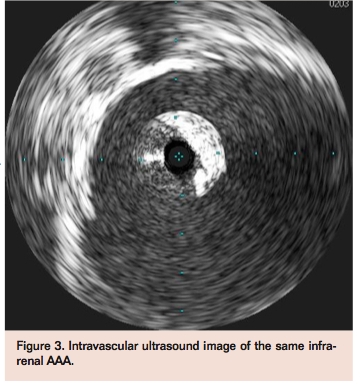

VASCULAR DISEASE MANAGEMENT 2013:10(8):E138-E141

The patient was brought to the catheterization laboratory, prepped, and draped in sterile fashion for percutaneous access. Micropuncture access was obtained in bilateral femoral arteries with placement of 6 Fr sheaths bilaterally. Selective angiograms confirmed common femoral artery access with minimal disease and a Prostar XL Percutaneous Vascular Surgical device (Abbott Vascular) was predeployed to deliver sutures at each puncture site for hemostasis at completion of the procedure. Descending aortogram confirmed a distal AAA with a long infrarenal neck (Figure 2). Intravascular ultrasound imaging (IVUS) corroborated findings (Figure 3) from the CT angiogram and aortogram. An Ovation 26 mm aortic body stent graft (TriVascular) was selected due to the low-caliber 14 Fr outer diameter of this device, and advanced sheathless via the right femoral artery.